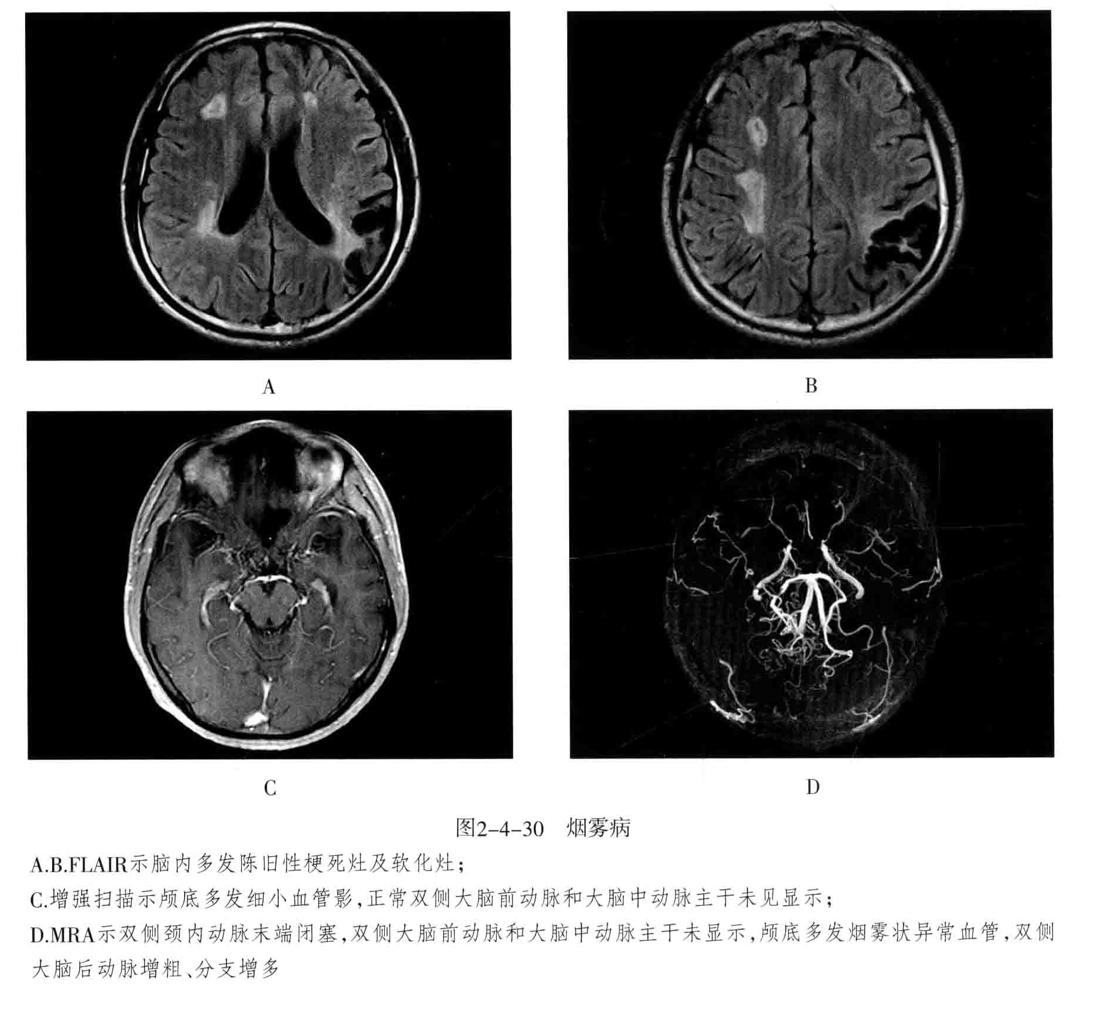

十、烟雾病

又称为脑底异常血管网症、脑底动脉环闭塞症。是以脑内虹吸段至大脑前、中动脉近端狭窄或闭塞,同时伴有广泛侧支循环形成,导致颅底出现异常毛细血管网为特征的脑血管病。好发年龄10岁以下和40-50岁。临床表现为脑缺血和脑出血两大类。儿童多为颈内动脉系统缺血性改变,成人多为颅内出血。

1. CT平扫表现为双侧额叶、顶叶及颞叶皮质或皮质下区多发脑梗死及脑萎缩改变,也可以出现颅内出血。增强有时可见到颈内动脉及大脑前中动脉粗细明显不对称,或者充盈不良,甚至不显影。可显示基底池及基底节区的侧支循环网,大多表现为为不规则的扭曲成团的强化血管影。

2. MRI表现为脑缺血引起的T1WI低、T2WI高信号脑梗死区,颈内动脉及大脑中动脉主干的“流空效应”变弱或消失,异常血管网在T2WI上表现为基底节区和鞍上池内多发细小血管影,呈网状低信号或无信号区。皮质侧支循环形成时,增强扫描可见皮质血管增多、扩张、强化、呈“常春藤征”。

3. MRA可直接显示颈内动脉、大脑前、中动脉狭窄或闭塞,于颅底见烟雾状异常血管网,常可见到颈外动脉和椎-基底动脉分支代偿性增粗。

4. 脑血管造影是确诊烟雾病的主要检查方法,可显示狭窄或闭塞的动脉及异常扩张的血管网。